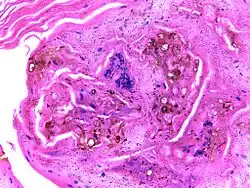

Micrograph of chromoblastomycosis showing sclerotic bodies | |

The most informative test is to scrape the lesion and add potassium hydroxide (KOH), then examine it under a microscope. (KOH scrapings are commonly used to examine fungal infections.) The pathognomonic finding is observing medlar bodies (also called muriform bodies or sclerotic cells). Scrapings from the lesion can also be cultured to identify the organism involved. Blood tests and imaging studies are not commonly used. On histology, chromoblastomycosis manifests as pigmented yeasts resembling "copper pennies". Special stains, such as periodic acid Schiff and Gömöri methenamine silver, can be used to demonstrate the fungal organisms if needed.